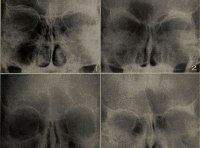

Одесса была в числе первых центров нового направления медицины – рентгенологии. 8 марта 1925 года основано Одесское научное общество рентгенологов.Так, доктор Яков Моисеевич Розенблат прошел курс специализации по вопросам медицинской химии в лабораториях Берлина и в Институте Пастера (Париж). По возвращении он основал в Одессе один из первых в России Частный химико-бактериологический институт.

Кроме того, в 1910 году в Одессе основана первая в России радиологическая лаборатория, под руководством Евгения Самойловича Бурксера.

Яков Розенблат стал одним из ведущих специалистов Европы по рентгенологии. Он же стоял у истоков организации кафедры рентгенологии в рамках Одесского клинического института, а впоследствии и в Медине. Назначенный заведующим кафедры, утвержденный в звании профессора Я.М.Розенблат читает студентам Медицинского института цикл лекций по основам рентгенологической специальности.

В Одессе была основана школа рентгенологов. Ее представители — видные ученые и практики: Яков Иосифович Каминский, Николай Николаевич Исаченко, Ефим Давидович Дубовый, Иосиф Яковлевич Балабан и многие другие специалисты в крайне нужной, но и опасной, отрасли медицины.